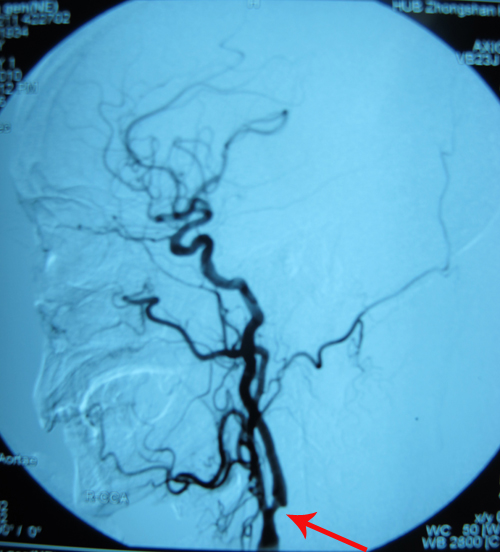

DSA示:右颈内动脉起始部中重度狭窄;左侧颈内动脉起始部粥样斑块形成。

该患者右侧颈内动脉中重度狭窄,且出现TIA症状,符合颈动脉内膜剥脱术手术指征。2010年12月20日,由协作组张勤奕教授与安贞医院欧阳川教授顺利为其实施了右侧颈内动脉内膜剥脱术。